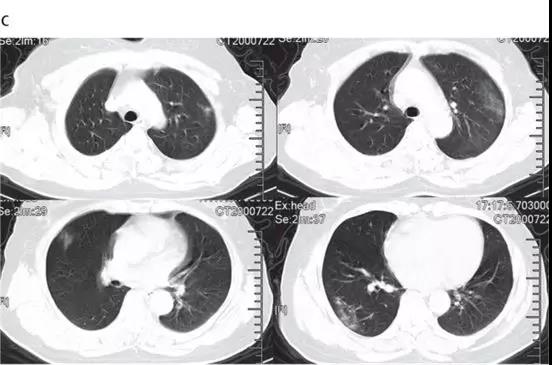

ICU患者入院時胸部CT圖像的典型發現,是雙側多發小葉和亞段實變(見下圖)。